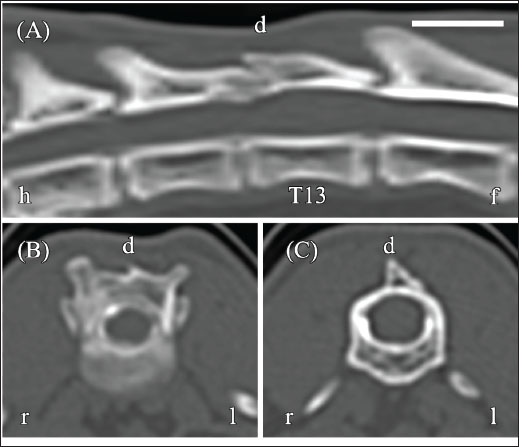

CT myelography was performed using an Alexion CT scanner (Canon Medical Systems, Otawara, Japan) to evaluate the relationship of the fluid-filled lesion (slice thickness, 1.0 mm; reconstruction kernel, FC30). Iohexol (Omnipaque 240) was administered via lumbar puncture at a dose of 0.4 ml/kg under CT guidance. Scans were obtained approximately 5 minutes after the injection. The contrast distribution and the presence or absence of extradural/intradural filling defects were assessed. A bone tissue window (window width, 3,000 HU; window level, 500 HU) was used for analysis. CT revealed thickening of the dorsal vertebral arch associated with the T13 fracture, but no vertebral misalignment. CT myelography showed no narrowing or rupture of the contrast medium column (Fig. 3A–C), suggesting an intramedullary lesion.

Fig. 3. CT myelography of the thoracolumbar vertebrae on day 1. (A) Sagittal reconstructed CT myelography shows no obvious spinal cord compression. (B) Transverse image at the T12–T13 level shows an intact contrast medium column without deformation. (C) Transverse image at the T13 level shows an expanded contrast medium column. Images were acquired using a bone tissue window (window width, 3,000 HU; window level, 500 HU). Orientation markers: h=head, f=foot, r=right, l=left. Scale bar=1 cm.